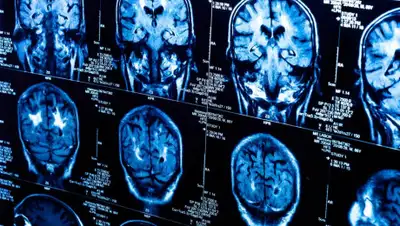

Врачи говорят, что эту опухоль трудно диагностировать. Она не сопровождается головными болями или зрительными нарушениями. Единственный звоночек – это повышенная выработка гормонов. Гульзинат сделали магнитно-резонансную томографию, которая подтвердила опухоль в гипофизе. Операцию женщине провели с применением современных методов лечения – через нос.